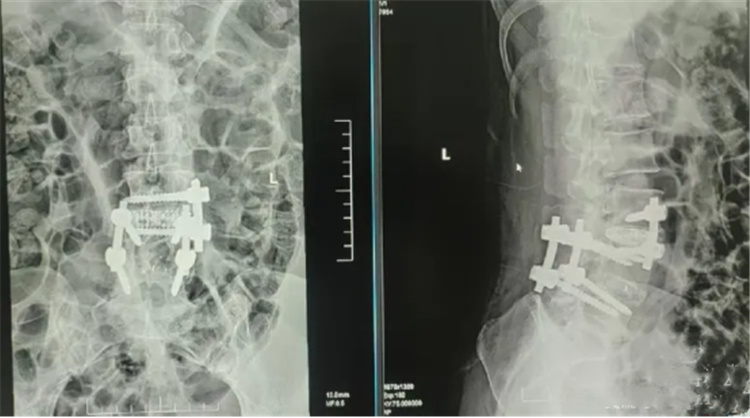

图片

术前影像资料